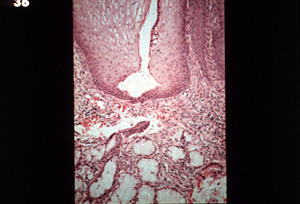

Esta microfotografía muestra el conducto dilatado sin la formación de queratina.

Debajo hay vasos dilatados e  inflamación crónica en el tejido de la glándula salival.